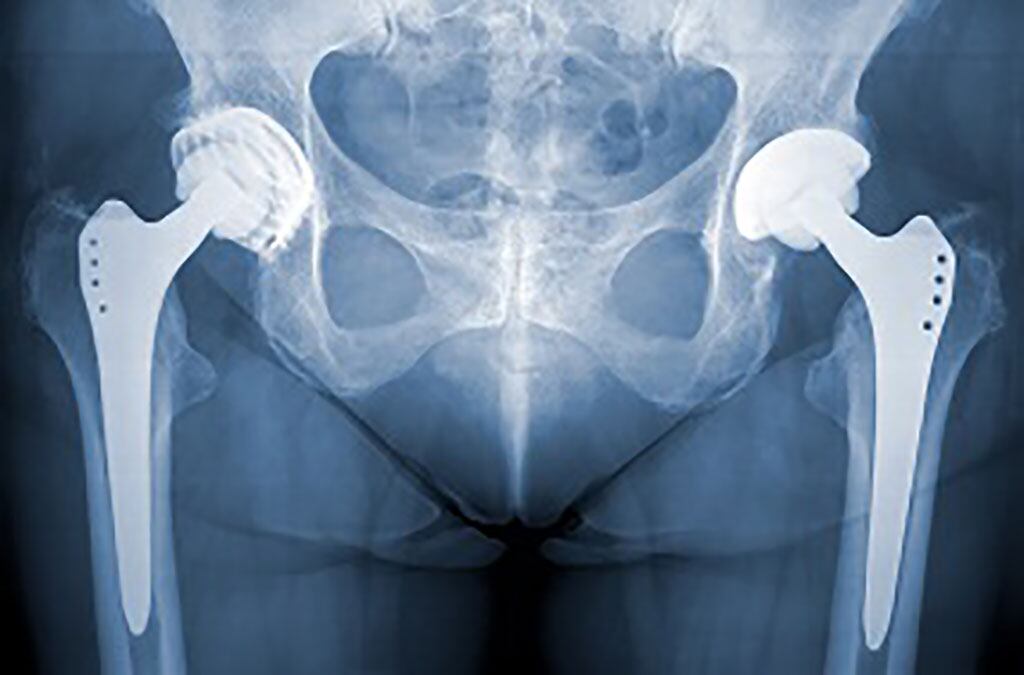

Sustitución de cadera

La Gerencia de Asistencia Sanitaria de Soria ha publicado en la Plataforma de Contratación del Sector Público la adjudicación de la realización de procedimientos quirúrgicos de traumatología (sustitución total de cadera y sustitución total de rodilla), para pacientes con derecho a prestación sanitaria pública en el Área de Salud de Soria, a Hospital Moncloa Grupo HLA, S.A.U., de Madrid, por un importe estimativo de 266.000 euros.

La adjudicación supone la concertación externa de 41 procesos de sustitución total de rodilla y 20 de cadera. Este concierto tiene un plazo de ejecución de tres meses desde la firma del correspondiente contrato previsiblemente a partir del 5 de agosto de 2022.